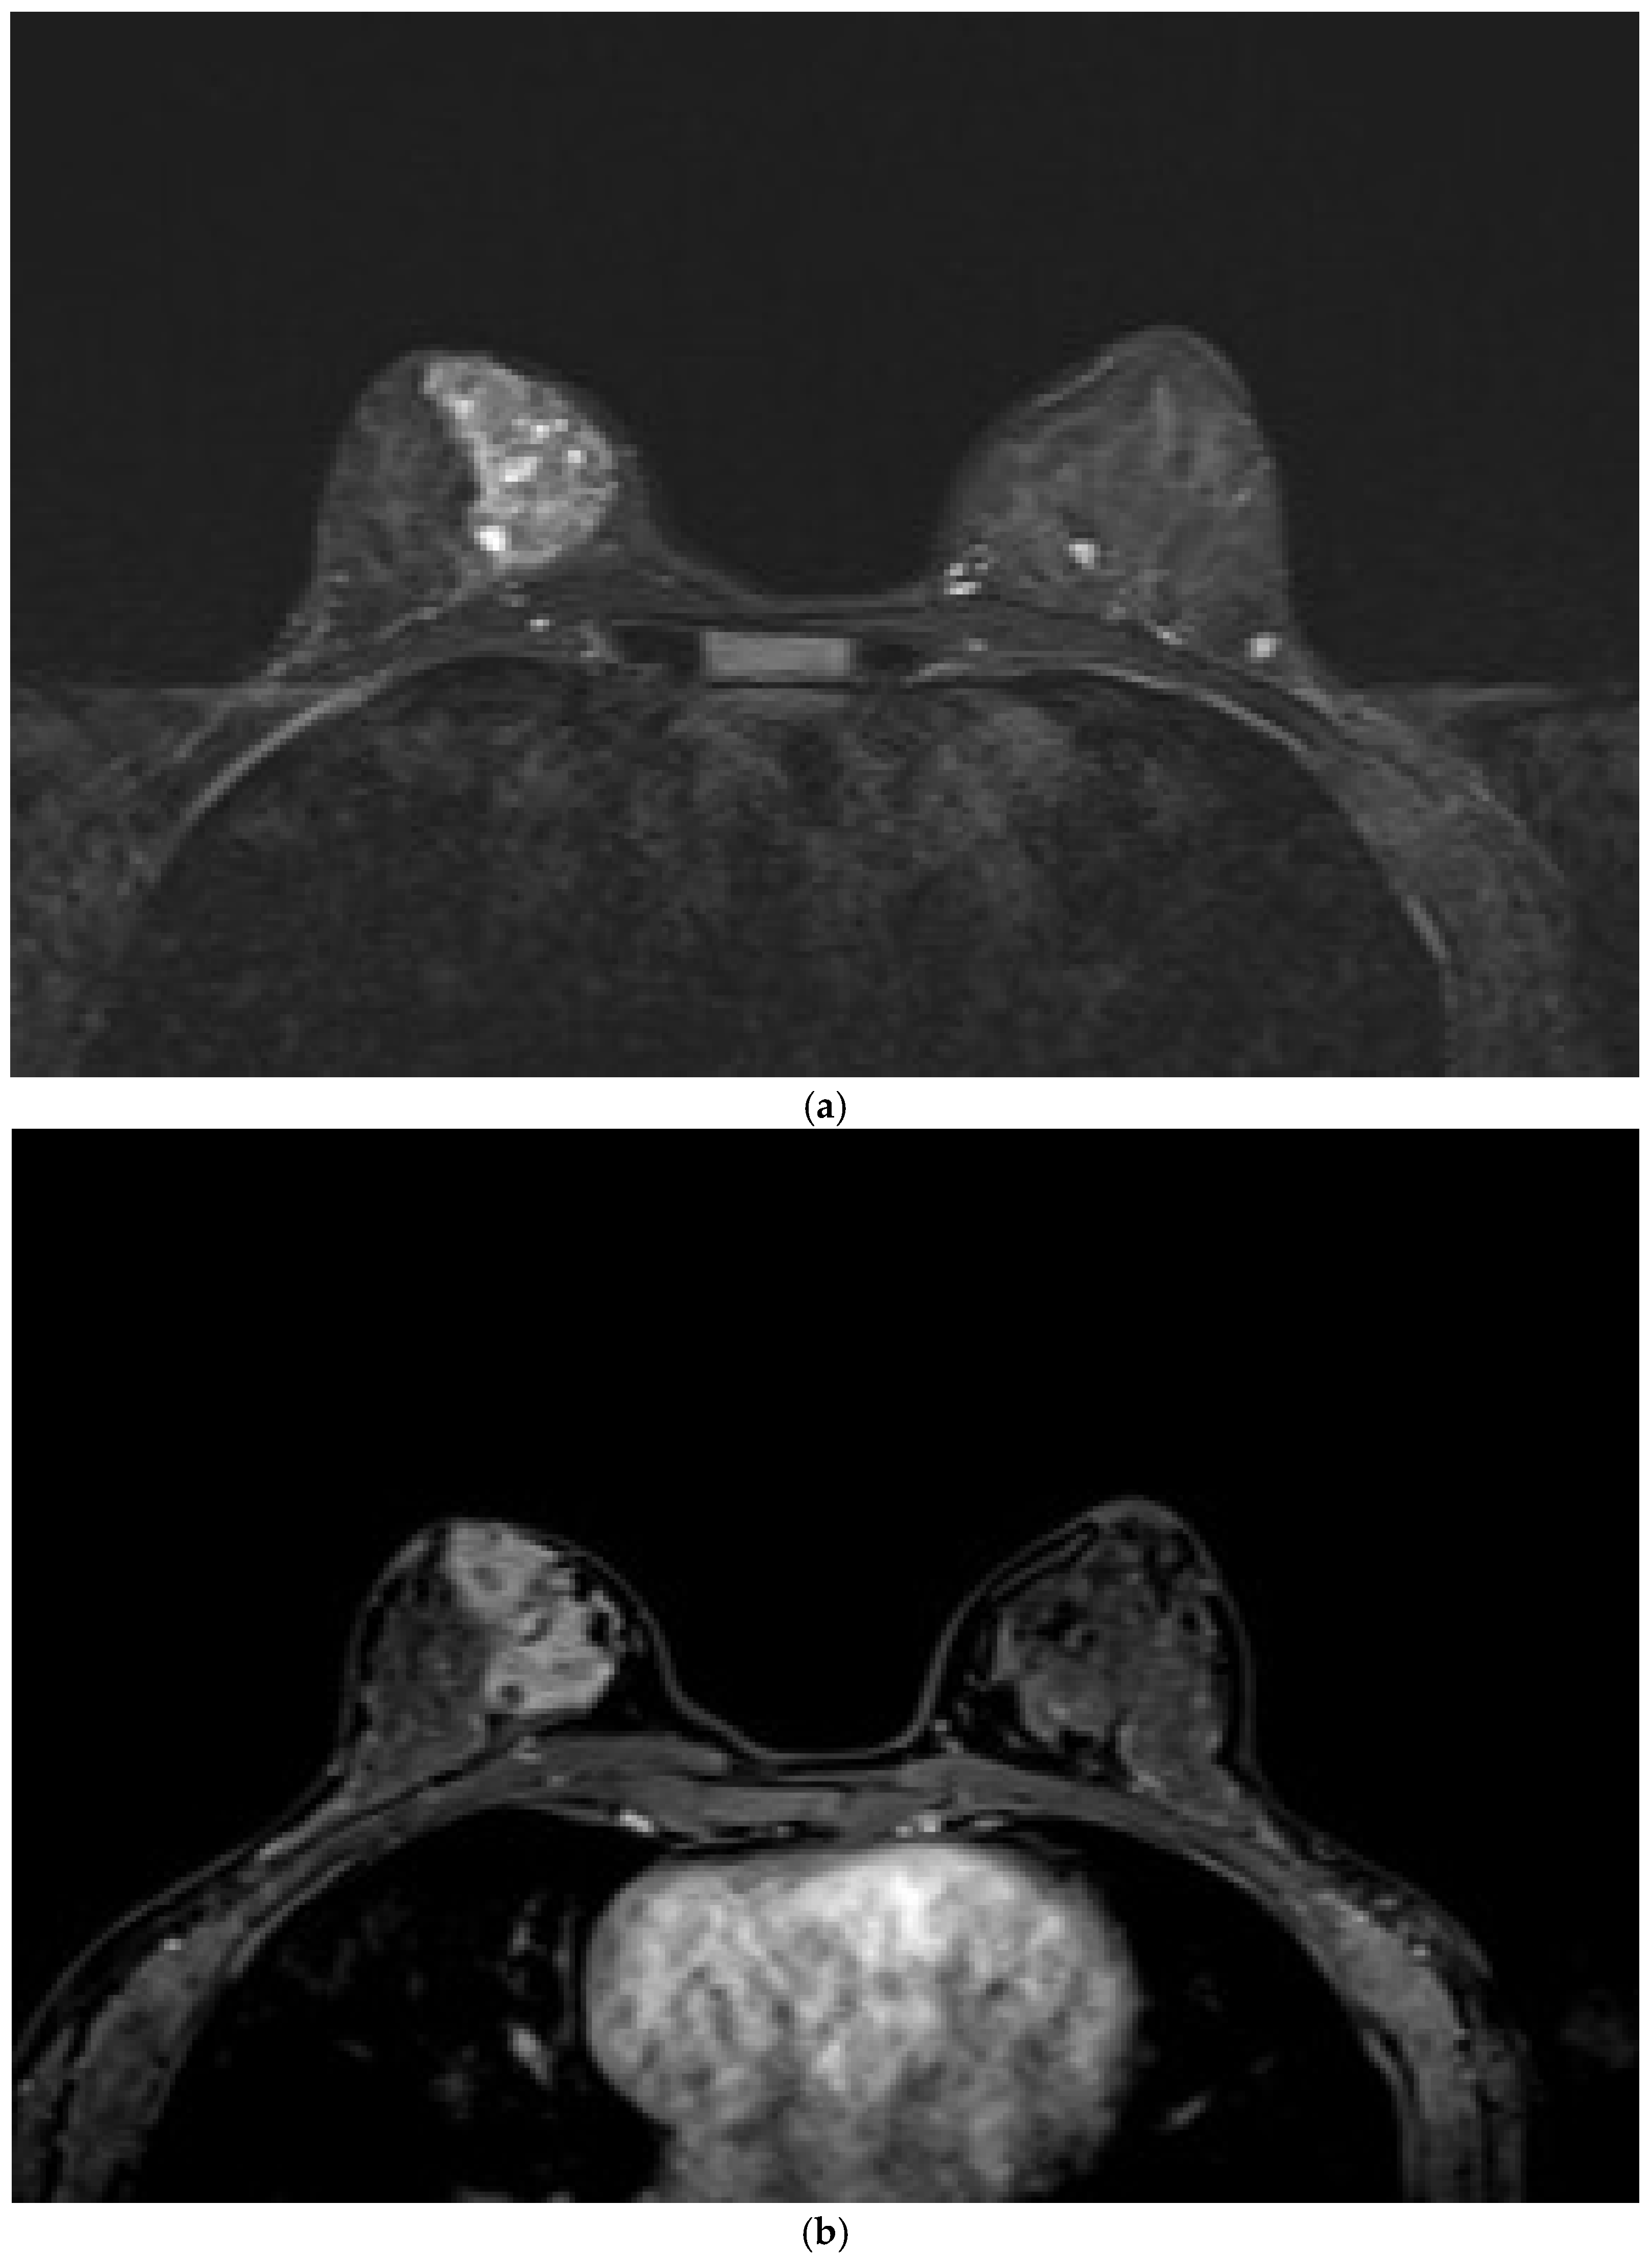

NME lesions with segmental distribution were evaluated according to the ACR BI-RADS 5th edition lexicon [1]. CRE was the second most common pattern after heterogeneous enhancement and the most frequent IEP in malignant lesions, with statistical significance (p < 0.05). The PPV of CRE was 87.5% (95% CI, 76.8–98.2), which is consistent with the literature. Its specificity was 88% (95% CI, 74.2–94.4), which is higher than the values reported in the literature. This discrepancy might be attributed to the fact that our study focused solely on segmental NME lesions with the highest PPV. Segmental NME forms a distinctive pyramidal configuration, with the apex aligning toward the nipple and the base extending toward the chest wall (Figure 4). Previous studies have clearly reported a strong association between segmental NME and DCIS [3,4,8,9,10,15]. Table 3 summarizes previously reported histopathologic diagnoses associated with segmental NME lesions for contextual reference.

Figure 4. Breast magnetic resonance imaging of a 46-year-old woman demonstrating segmental nonmass enhancement in the lower outer quadrant of the right breast. The lesion displays a clumped internal enhancement pattern. Histopathological evaluation confirmed ductal carcinoma in situ.